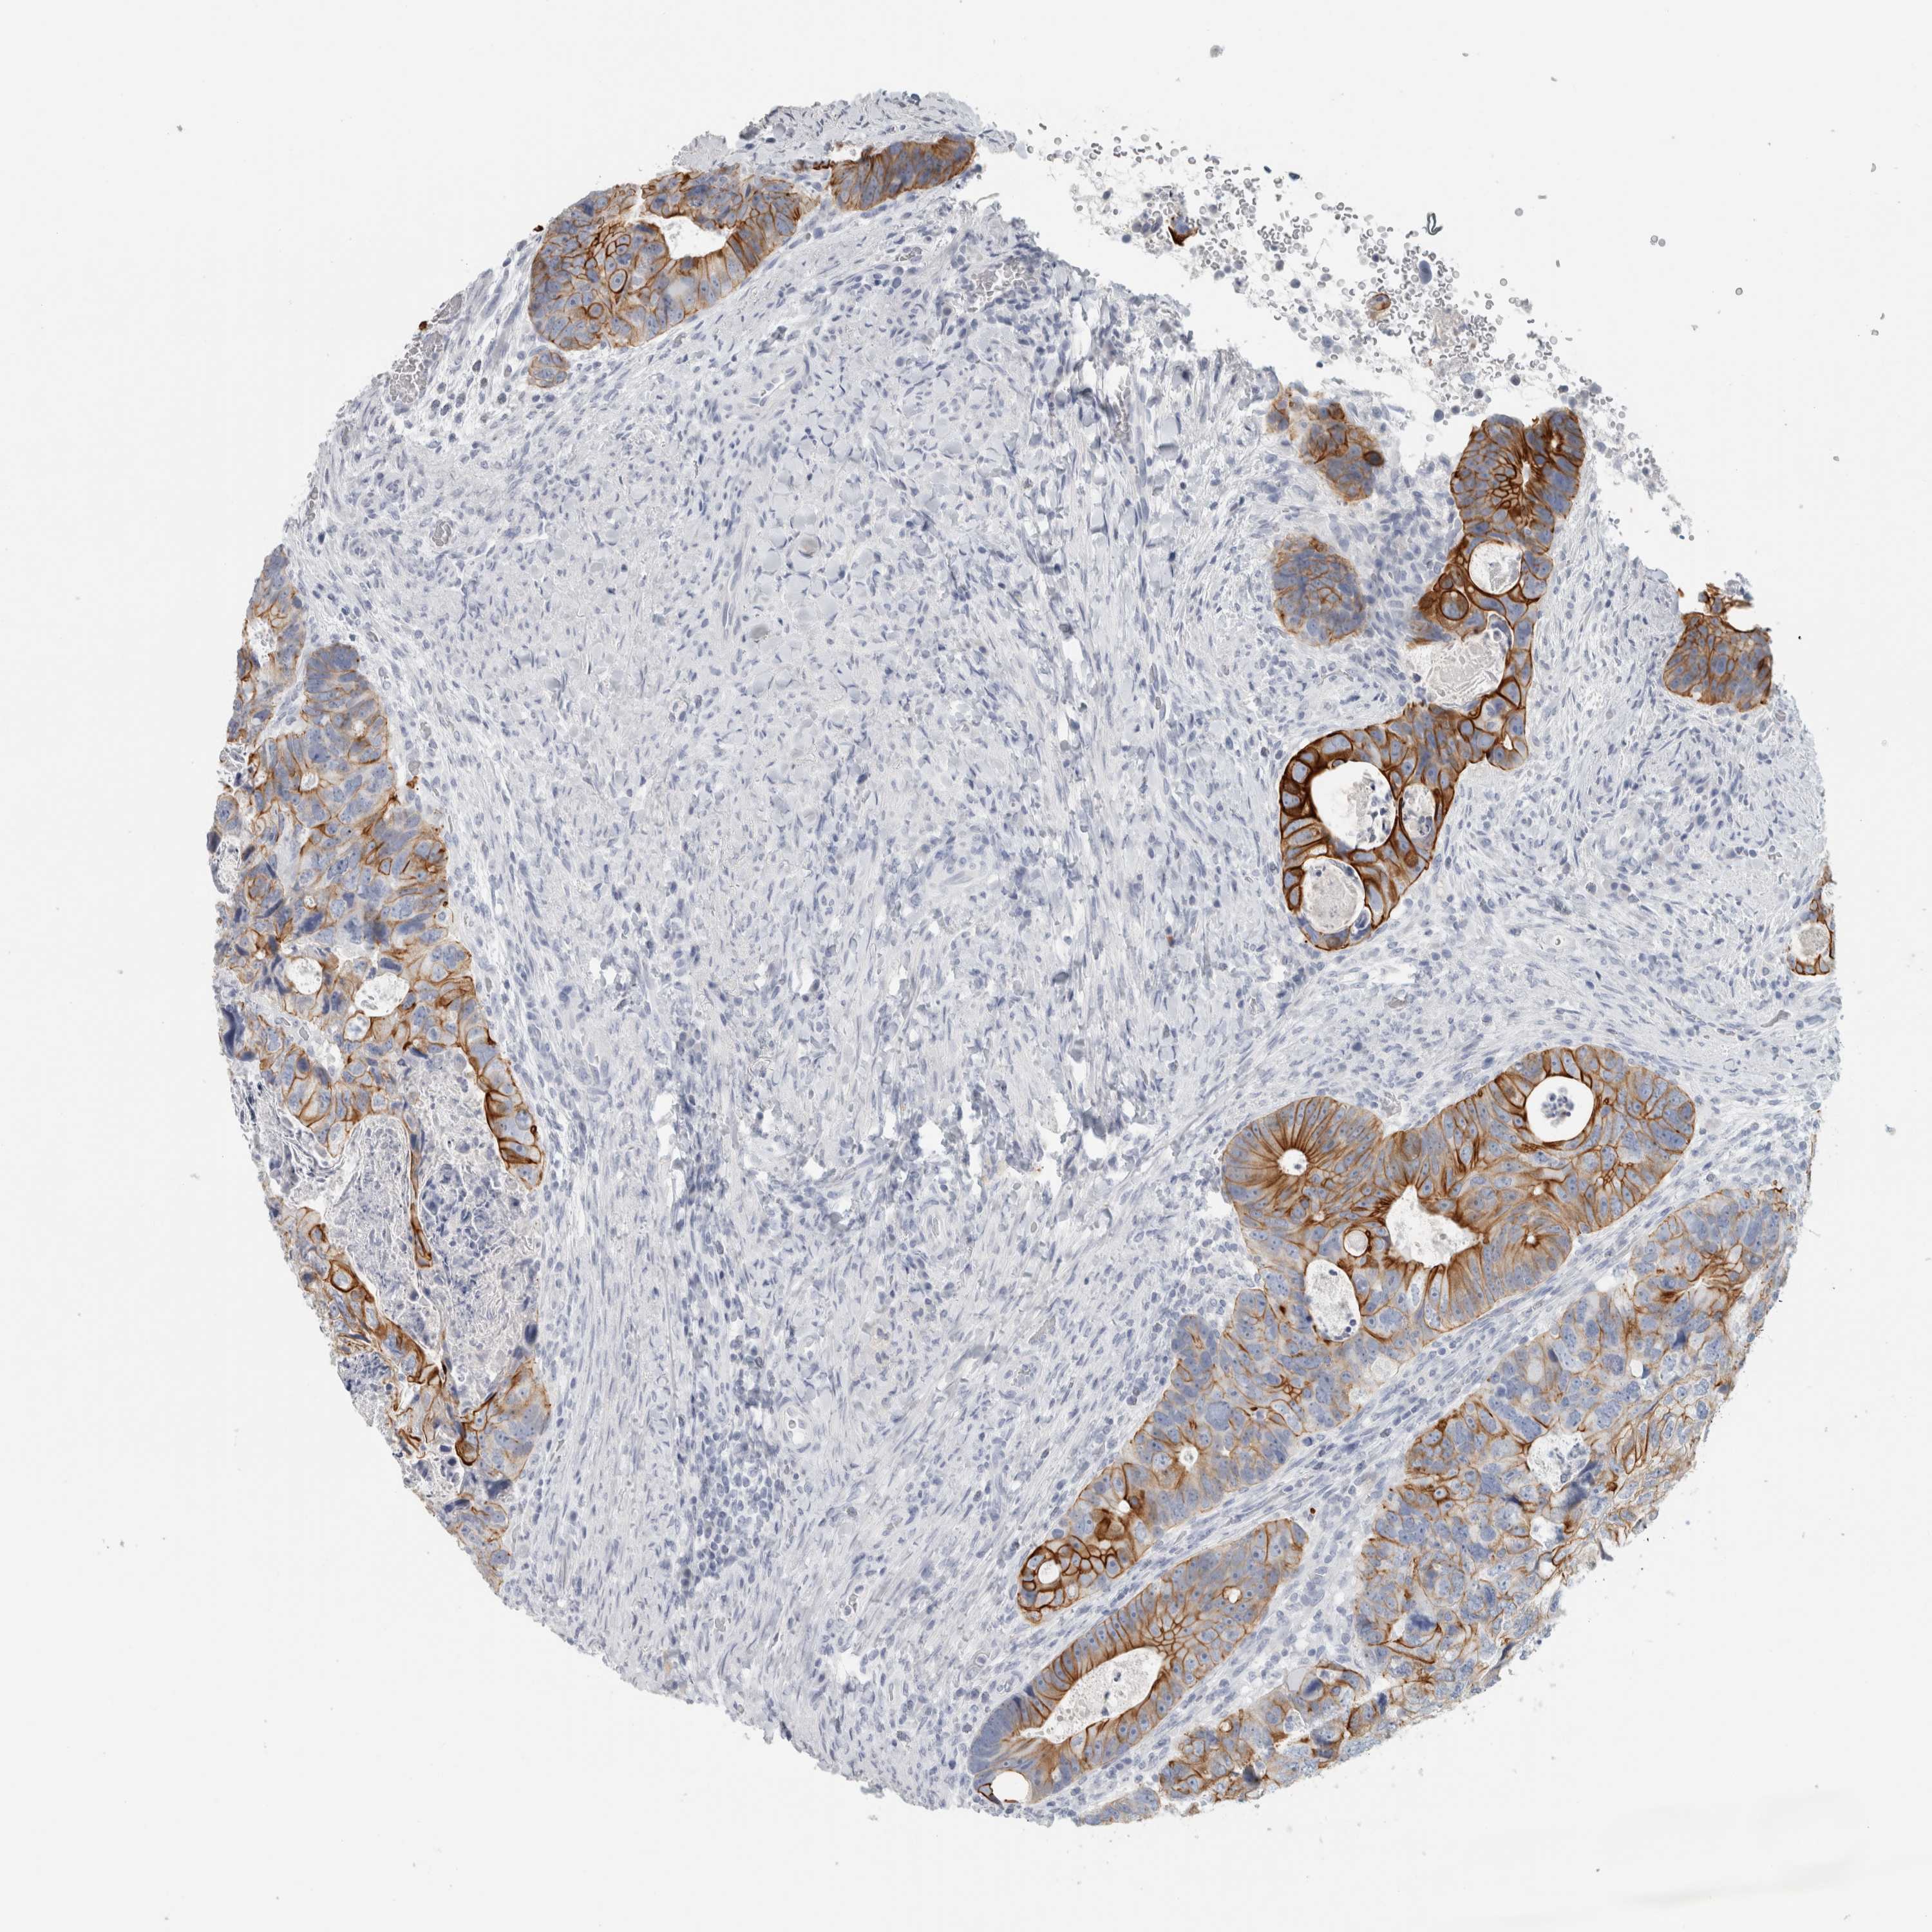

CANCER COLORECTAL CANCER Show tissue menu

Colorectal cancer

Human cancer

Colon adenocarcinoma